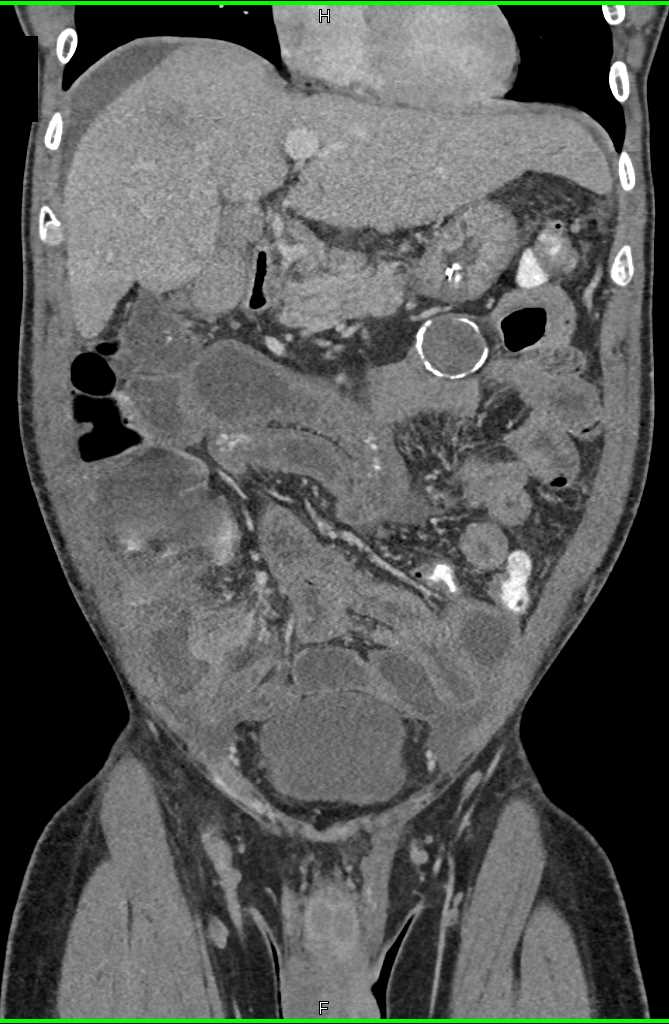

Small Bowel Carcinoma with Carcinomatosis